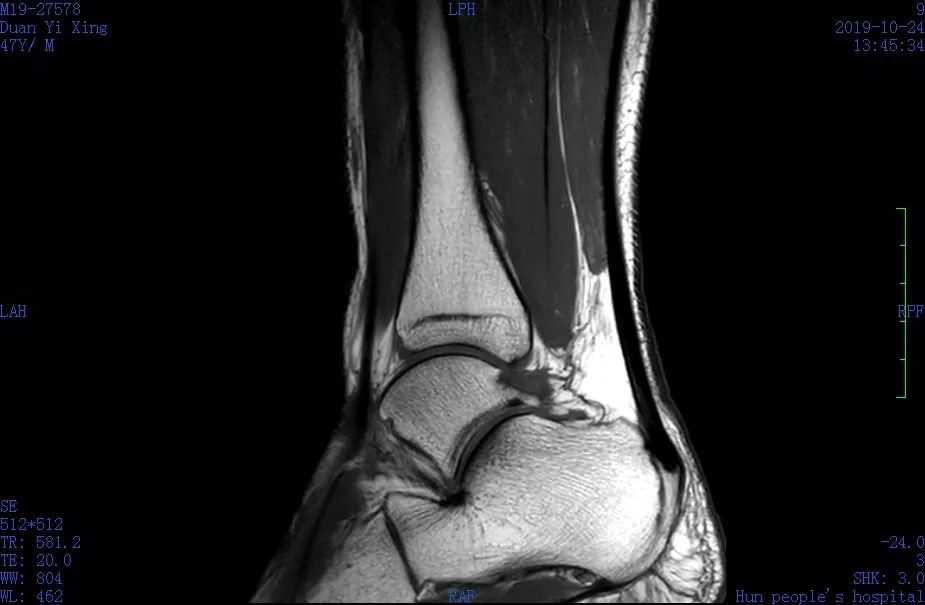

▲磁共振显示韧带撕裂、跟腱损伤。

同事立即找来轮椅,推着他前往骨科和放射科看病、做检查。急诊磁共振检查显示“左踝外侧副韧带撕裂,距腓后韧带损伤,左踝跟腱损伤,左踝关节周围软组织肿胀”。骨科医生为他进行石膏外固定后,叮嘱他要制动4~6周。